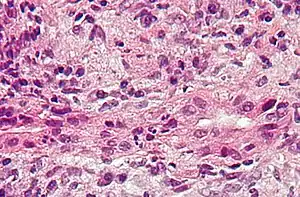

Intermediate-magnification micrograph of PBC showing bile duct inflammation and periductal granulomas, liver biopsy, H&E stain

On microscopic examination of liver biopsy specimens, PBC is characterized by chronic, nonsuppurative inflammation, which surrounds and destroys interlobular and septal bile ducts. These histopathologic findings in primary biliary cholangitis include:[31]

- Inflammation of the bile ducts, characterized by intraepithelial lymphocytes

- Periductal epithelioid granulomas.

- Proliferation of bile ductules

- Fibrosis (scarring)